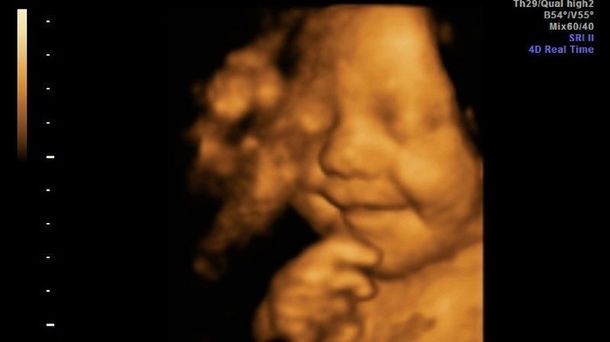

El bebé más feliz del mundo ya sonreía en la panza

Se trata de Leo Hargreaves, quien tenía solo 31 semanas al momento de haber sido tomada la captura a través de la ecografía 4D.

"Mi pareja Leighton y yo estábamos absolutamente sorprendidos. Pero esa ecografía fue sólo el principio, porque desde que nació no para de sonreír, incluso cuando está durmiendo", dijo Amy Cregg, la mamá, al Daily Mail.

La imagen se viralizó y comenzó a recorrer la web. Millones de personas en el mundo la vieron, se emocionaron y las agencias de publicidad no se quisieron quedar afuera. Su madre comenta que muchos la contactaron para usar la sonrisa.